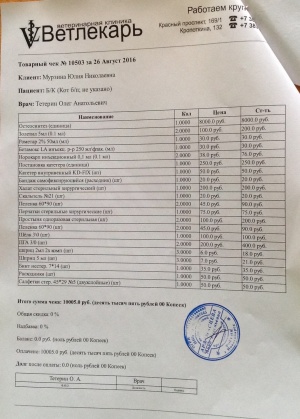

Финальный отчёт.

Период отчёта: 10.07.16-26.08.16

Приход:

Благотворительница Stavr45 - 1000 рублей;

Благотворительница Александра_R - 500 рублей;

Влад18 - 8845 рублей;

Итого: 10345 рублей.

Расход:

Операция 10005 рублей (чек1);

Сутки стационара - 340 рублей (чек2);

Итого: 10345 рублей.

Остаток на 26.08.16 - 0 рублей.

Период отчёта: 10.07.16-26.08.16

Приход:

Благотворительница Stavr45 - 1000 рублей;

Благотворительница Александра_R - 500 рублей;

Влад18 - 8845 рублей;

Итого: 10345 рублей.

Расход:

Операция 10005 рублей (чек1);

Сутки стационара - 340 рублей (чек2);

Итого: 10345 рублей.

Остаток на 26.08.16 - 0 рублей.